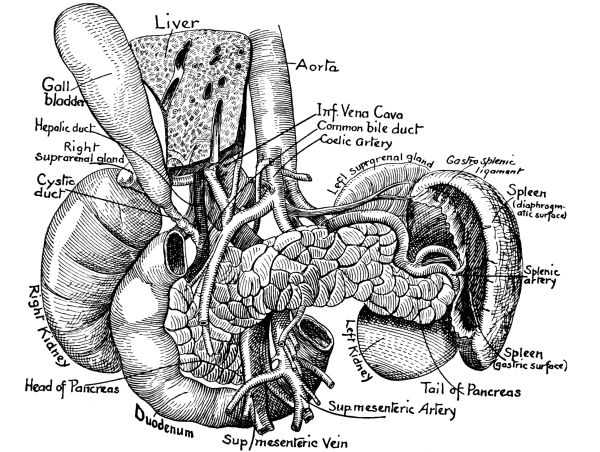

The Abdominal Cavity, 132—Muscles of the Abdomen, 132—The Peritoneum, 134—Abdominal Regions, 134—Salivary Digestion, 136—The Pharynx, 139—The Esophagus, 138—The Stomach, 138—Gastric Digestion, 139—Vomiting, 140—Intestinal Canal, 141—The Small Intestine, 142—Intestinal Digestion, 143—Absorption in Intestine, 144—The Large Intestine, 145—Food and Metabolism, 147—The Liver, 149—The Gall-bladder, 152—The Pancreas, 153—The Spleen, 153—The Suprarenal Capsules, 154—The Kidneys, 155—The Urine, 156—The Ureters, 159—The Bladder and Urethra, 159. |